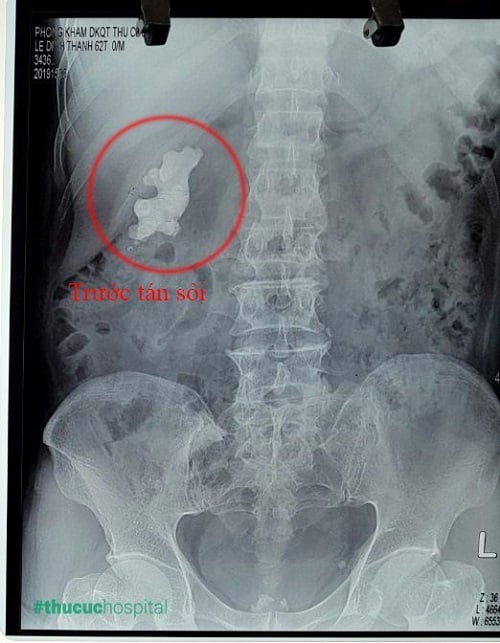

– Không nên vừa ăn hải sản vừa uống bia: hải sản luôn được xem là “mồi” ngon để nhậu bia đồng thời nhiều người nghĩ bia sẽ giúp dễ tiêu hóa hơn khi ăn hải sản. Tuy nhiên, tôm, cua, ghẹ và các loại hải sản khác khi gặp men bia dễ làm tăng hàm lượng Acid Uric (nguyên nhân gây bệnh sỏi thận, bệnh gout…).